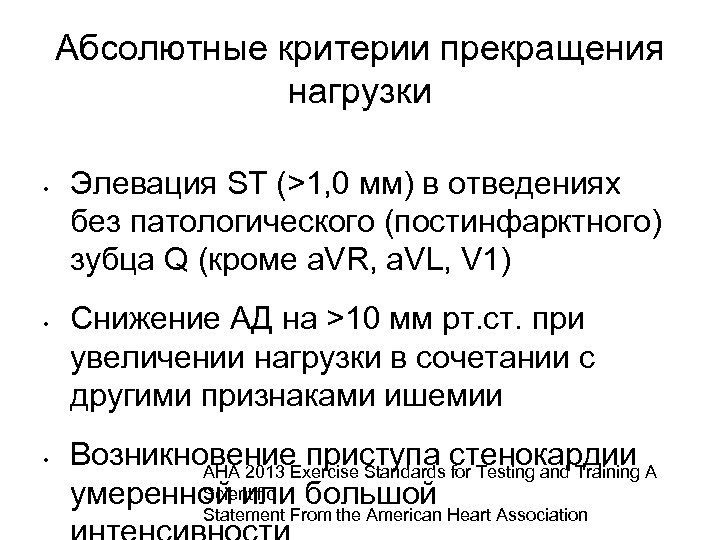

Абсолютные критерии прекращения нагрузки • • • Элевация ST (>1, 0 мм) в отведениях без патологического (постинфарктного) зубца Q (кроме a. VR, a. VL, V 1) Снижение АД на >10 мм рт. ст. при увеличении нагрузки в сочетании с другими признаками ишемии Возникновение приступа стенокардии AHA 2013 Exercise Standards for Testing and Training A Scientific умеренной или большой Statement From the American Heart Association

Абсолютные критерии прекращения нагрузки • • • Элевация ST (>1, 0 мм) в отведениях без патологического (постинфарктного) зубца Q (кроме a. VR, a. VL, V 1) Снижение АД на >10 мм рт. ст. при увеличении нагрузки в сочетании с другими признаками ишемии Возникновение приступа стенокардии AHA 2013 Exercise Standards for Testing and Training A Scientific умеренной или большой Statement From the American Heart Association